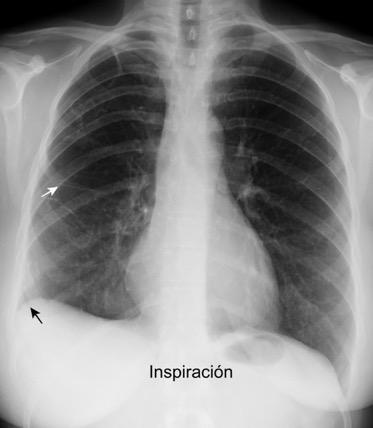

91. NEUMOTÓRAX EN ESPIRACIÓN

Visualización de la pleura visceral separada de la parietal por aire Borde externo Convexo Localización: Ápex pulmonar

M. Bradley et al. Value of routine expiratory chest films in the diagnosis of pneumothorax.Arch Emerg Med.1991, F. Schramel, et al. Expiratory chest radiographs do not improve visibility of small apical pneumothoraces by enhanced contrast.Eur Respir J. 1996,